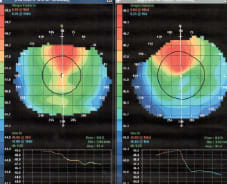

Figure 2. A patient who has moderate keratoconus with irregular corneal cylinders of 4.00D and 5.00D. The I/S here for both the right eye and the left eye is 2.88D.

Figure 3. A patient who has a more concentrated and a more diffuse central cone. The I/S values here differed: OD 1.99D, OS 2.47D.